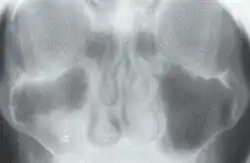

Axiale transverse Röntgen-Stratigraphie des Mittelgesichts: der Grauschleier entsteht durch die unscharf abgebildeten Ebenen, die sich vor und hinter der scharf dargestellten Ebene befinden und daher als Verwischungsstruktur erscheinen.

1930 entwickelte er die Grundlagen der Tomographie, die er selbst als axiale transverse Röntgen-Stratigraphie bezeichnete.[2][3][4] Dazu ließ Vallebona eine Röntgenquelle und einen Film gegenläufig um einen Patienten laufen, so dass nur die im Drehpunkt liegende Ebene scharf abgebildet wurde. Die weiteren Ebenen vor und hinter der scharf abgebildeten Ebene erschienen auf dem Röntgenbild aufgrund ihrer Bewegungsunschärfe als Verwischungsstrukturen. Moderne Tomographen verwenden einen Computer, um jene Verwischungsstrukturen aus dem Röntgenbild herauszurechnen. 1970 wurde A. Vallebona mit der Röntgen-Plakette ausgezeichnet.